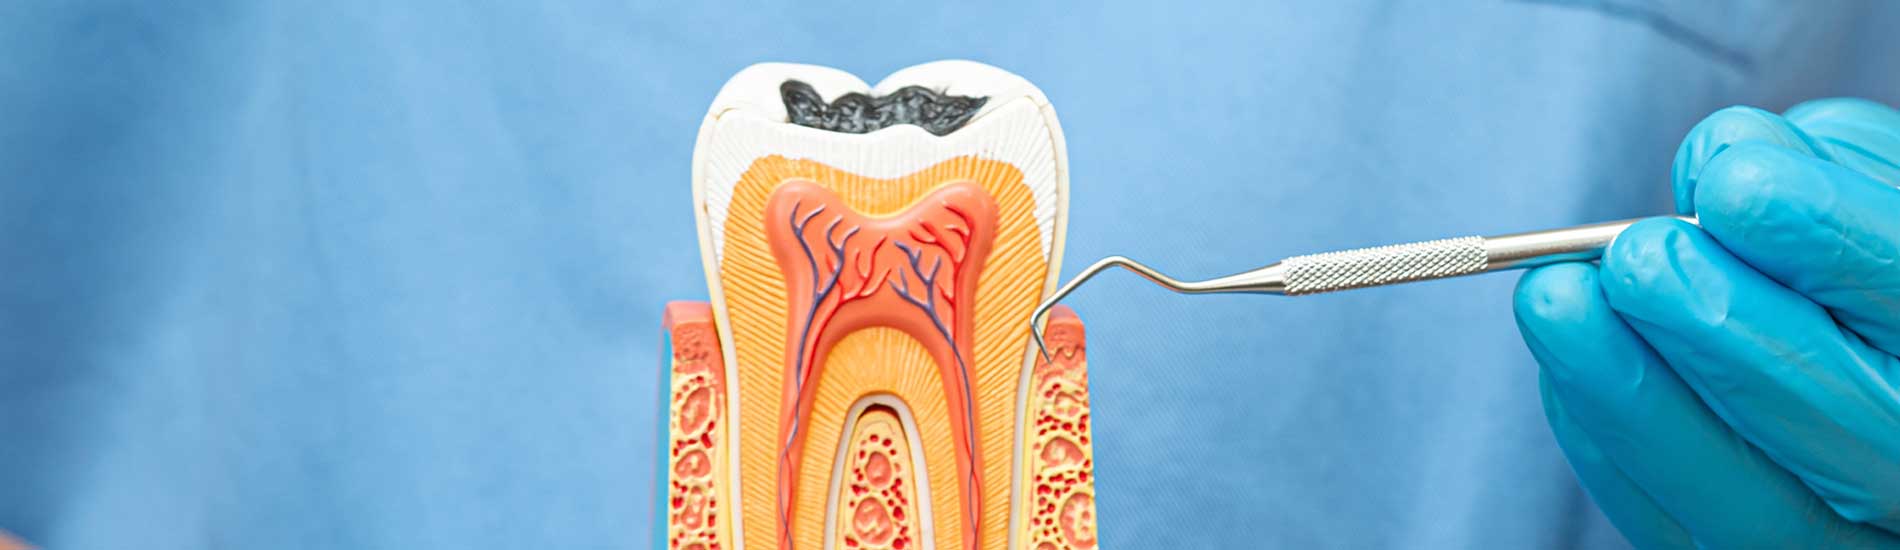

Advanced Technology

We utilize state-of-the-art technology in order to provide all of our patients with the best dental experience possible.